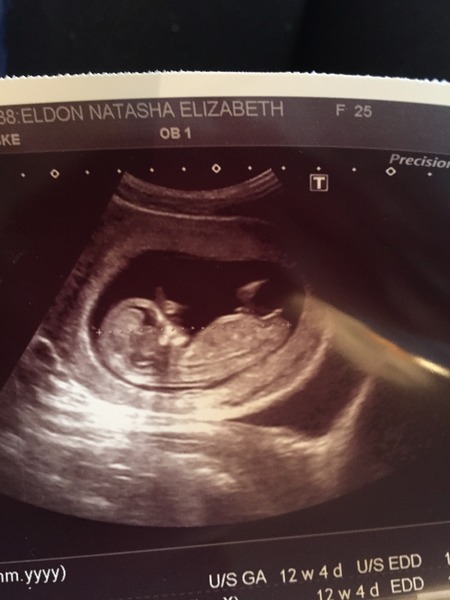

I'm not so sure but I'd lean towards girl. Can u have a guess on mine please? :) xx

kizulo looks girly to me too. Nub is horizontal to the spine. X

Kizulo I'd say boy for you too as it looks like stacking on the nub. would love updates on all these.